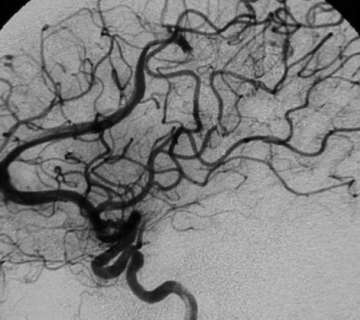

Not all AVMs require embolization. Prior to treatment, there is a discussion between the treating physicians as to whether embolization will be helpful in a particular AVM. Only if deemed useful, is embolization performed (Figures 5. and 6.) It is understood that embolization has its own risks apart and separate from the risks of surgery or radiation. Therefore, if not useful, it is not prudent to expose the patients to the risk of embolization on top of the risk of surgery or radiation.